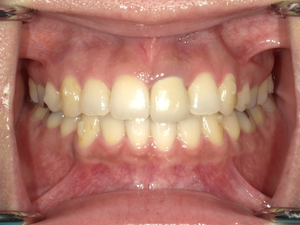

befor→after

●ご相談内容:歯の出っ張り●矯正の種類:マウスピース型矯正「インビザラインGO」●治療期間:13週間●治療費用:44万円(税込)